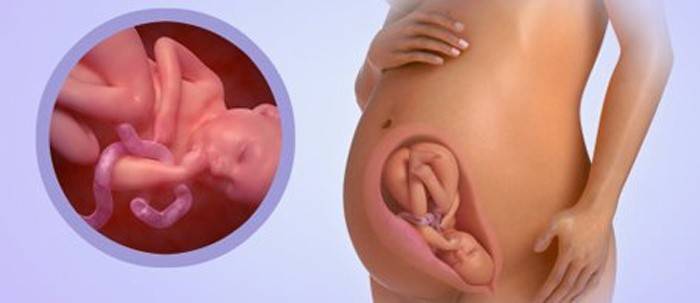

Vývoj plodu v 35. týždni: veľkosť a pohlavie

Dieťa do tejto doby vedie asi 2400 - 2600 g, rast presahuje 45 - 46 cm, hoci individuálne výkyvy sú možné na základe charakteristík vývoja, dedičnosti a výživy matky. Od tohto obdobia bude dieťa pridávať 200 - 250 gramov týždenne. V maternici je málo miesta pre dieťa a budete jasne cítiť všetky pohyby dieťaťa, niektoré pohyby môžu byť bolestivé, najmä oblasti rebier a pečene. Teraz sa dieťa nachádza v 98% žien s hlavou nadol s rukami a nohami privedenými k telu, a neexistuje spôsob, ako sa príliš natiahnuť a pohybovať, napína sa, krúti hlavou a pažami. Frekvencia pohybov by mala byť najmenej 10 pohybov za 12 hodín. Ak sú pohyby bolestivé a aktívne, alebo ak je dieťa veľmi tiché, mali by ste sa poradiť s lekárom, pravdepodobne plod nemá dostatok kyslíka.

Dovtedy boli všetky systémy a orgány aktívne vyvinuté, aktívne fungujú a pracujú na koordinovanej práci. Dodržiavanie podnetov nervového systému. Hormóny sa aktívne uvoľňujú v nadobličkách, ktoré podporujú výmenu vody a solí, ktoré regulujú fungovanie obličiek. Subkutánny tuk sa aktívne hromadí, najmä teraz sa deje v oblasti končatín, zatiaľ čo dieťa vyzerá ešte tenšie, ale po niekoľkých týždňoch sa výrazne zaokrúhli. Do dátumu narodenia sú deti bacuľaté a roztomilé, pokožka je ružová, hladká s jednotlivými vzormi na pätách a prstoch. Líca sú teraz okrúhle a nafúknuté, čo pomáha pri saní prsníkov. Dostatočne dlhé vlasy na hlave môžu dorásť späť, hoci dieťa sa môže narodiť s plešatou hlavou. Ale jeho obočie a dlhá riasina rástli. Nechty sa dostali na okraj vankúša a môžu byť dlhšie, čo vedie k tomu, že dieťa sa môže samovoľne poškriabať.

V tomto období dochádza v tele plodu k aktívnej akumulácii vápnika a železa, ktorá je nevyhnutná v prvých mesiacoch života dieťaťa pre jeho aktívny vývoj. Teraz je už dieťa schopné udržať teplo, ale stále mu hrozí podchladenie a je potrebná osobitná starostlivosť o takúto drobenku. Na tele prakticky neexistovali žiadne vlasy - lanugo a pôvodné mazanie zostalo iba v kožných záhyboch. U dievčat bola víla pyskov úplne pokrytá pyskami stydkých pyskov, u chlapcov semenníky spadli do mieška. Farba očí a vlasov dieťaťa nie je konečná, v prvom roku života zvyčajne menia farbu. Dieťa nezastaví svoj vývoj ani na minútu, jeho nervový systém sa stále formuje. Kosti lebky sú hustejšie, švy medzi nimi sa zmenšujú.